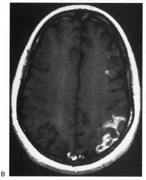

On the Boston Naming Test a subject is asked to name line drawings of objects (Fig. 22). The Visual Naming subtest of Multilingual Aphasia Exam requires the naming of photographs of objects. The Facial Recognition Test311 asks patients to select which of several pictures of faces, photographed at different angles and in different lighting conditions, match a target face (Fig. 23). Because these faces are unfamiliar, this tests face perception rather than face recognition. Face recognition can be tested by presenting pictures of presidents, movie stars, and famous athletes.